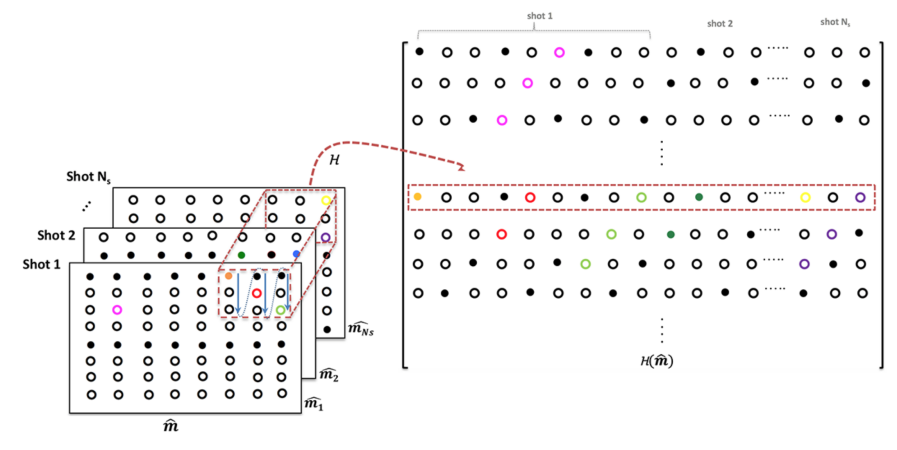

Here, is a block Hankel matrix of size generated from the Fourier samples of . Each of the rows of are vectorized versions of rectangular k-space neighborhoods of . Figure 2 shows the structure of the block-Hankel matrix. In practice, this mapping can be achieved using a sliding window operation as indicated in Figure 2. Similarly, is a vector of size , which is the vectorized version of the filter . Thus, provides a vector that corresponds to the convolution within the rectangular region . Note that this region corresponds to the valid convolutions between the filter and the samples of .

See figure 3 for an illustration of the new lifted matrix , which is highly low-rank. We propose to recover the motion-compensated multishot data using the consolidated nuclear-norm minimization problem that incorporates smoothness regularization (SR):

Fig 2: Illustration of the matrix lifting: is the k-space data matrix of a given DWI comprising of data from the different shots of the DWI. A sliding window of size as marked by the red dotted box generates the rows of the block-Hankel matrix by vectorizing the elements in the red block.

Fig 3: Illustration of joint matrix lifting for multi-shot data: The Fourier coefficients of the partial derivatives along the x-dimension and y-dimensions are obtained by multiplication using and , respectively. The block Hankel matrices of the each partial derivative are generated and and stacked as shown.